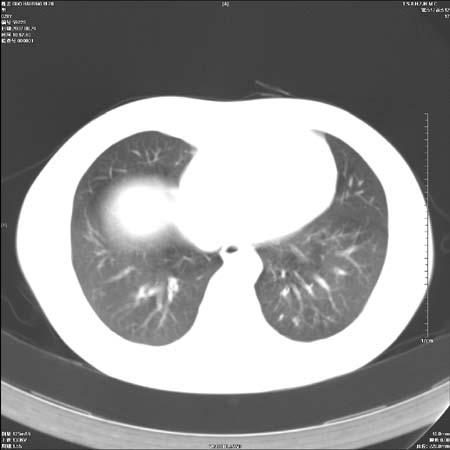

左肺肺门区肿块影,分叶明显:诊断肺癌应该没有疑问。

本例倾向周围型肺癌

鉴别:中央型肺癌-肿块那么明显一般合并节段肺不张或阻塞性炎症。

本例肿块边缘外侧可见左上叶各段支气管。

肺癌可能性大。(有分叶,毛刺)

左侧肺门区见一块状病灶可见分叶,纵隔内及左肺门见肿大淋巴结,应该是周围型肺癌而不是中心型肺癌,原因有以下2点,1未见阻塞肺气肿和阻塞性炎症,这么大肿块如果是中心型肺癌就是未分化型或小细胞型肺癌不出现阻塞性肺不张也应该有阻塞炎症或阻塞性肺气肿,2如果是中心型肺癌临床出现最早的症状是咳嗽(此时可无任何异常影象),而此人这么大肿块只有背部隐痛是体检才发现无法解释.